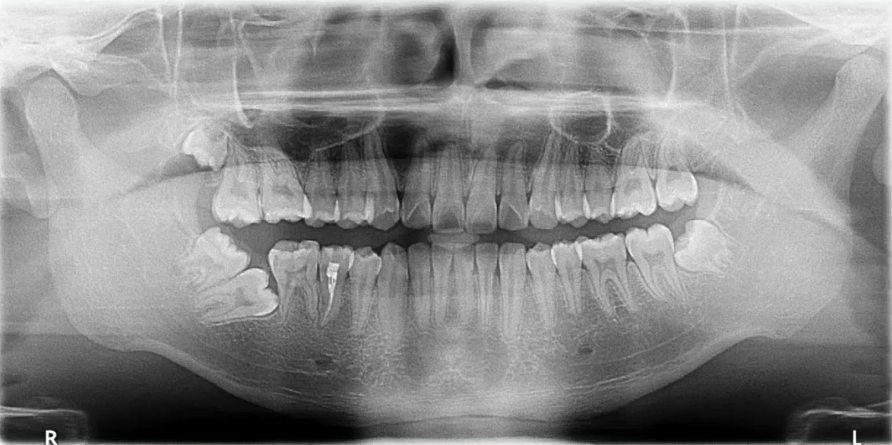

【病例4】

29岁,女性,自感牙体不适来院就诊

主要诊断:牙体——47龋坏伴根尖炎

牙列——35、45牙缺失,乳牙滞留,38、48智齿埋伏阻生

曲面断层片怎么看口腔精读 | 一次性教你看懂曲面断层片!_https://www.jmylbn.com_新闻资讯_第53张

根尖片进一步诊断

47龋坏伴根尖炎

曲面断层片怎么看口腔精读 | 一次性教你看懂曲面断层片!_https://www.jmylbn.com_新闻资讯_第54张

曲面断层片怎么看口腔精读 | 一次性教你看懂曲面断层片!_https://www.jmylbn.com_新闻资讯_第55张

37继发龋!根尖炎?

曲面断层片怎么看口腔精读 | 一次性教你看懂曲面断层片!_https://www.jmylbn.com_新闻资讯_第56张

曲面断层片怎么看口腔精读 | 一次性教你看懂曲面断层片!_https://www.jmylbn.com_新闻资讯_第57张

25远中邻面浅龋

曲面断层片怎么看口腔精读 | 一次性教你看懂曲面断层片!_https://www.jmylbn.com_新闻资讯_第58张